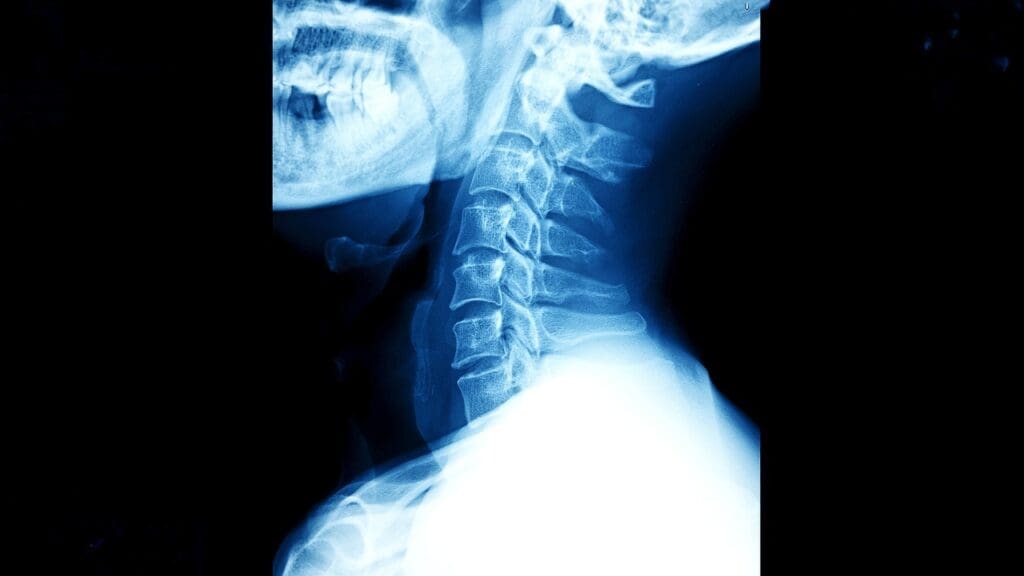

The cervical spine is a complex area that protects important nerves and helps us move our head and neck. Studies show that complications from cervical spinal surgery can happen in 10 to 25 percent of cases. This depends on the surgery type and the patient’s health.

The Reality of Cervical Spine Procedures

Cervical spine procedures are done to fix different problems, but they have risks. Surgery on the neck can change a person’s life a lot. Spine surgeries are chosen when other treatments don’t work or when there’s a big risk of getting worse.

Cervical spine surgeries can be done from the front, back, or both. The choice depends on the problem and the patient’s health.